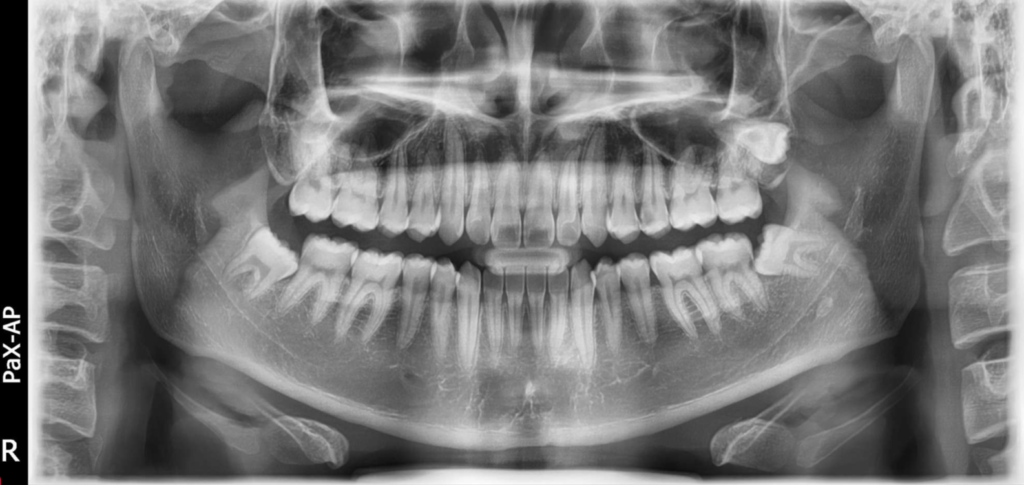

Insight es capaz de tomar una imagen panorámica de varias capas llamada Insight PAN que proporciona una mirada única a profundidad a través de un único canal focal.

Debido a que cada paciente puede tener un arco ligeramente diferente, las imágenes de panorámicas convencionales ocasionalmente pueden perder detalles importantes que salen de una sola capa focal.

Insight PAN es capaz de capturar una imagen panorámica de varias capas, asegurando que todos los detalles se capturen en una sola imagen panorámica.